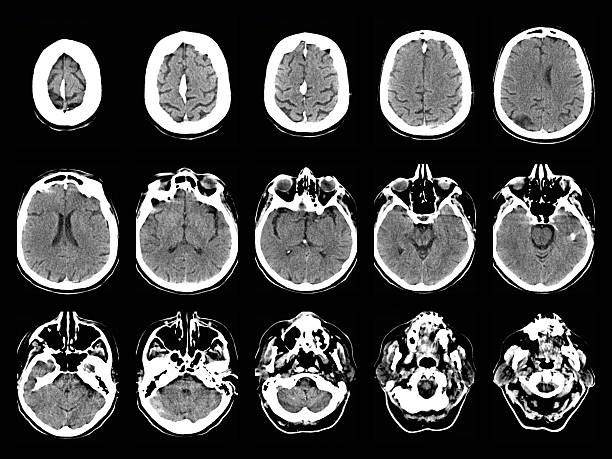

神經系統疾病,也稱為神經系統疾病或病癥,是影響中樞神經系統(大腦和脊髓)、周圍神經系統(大腦和脊髓以外的神經)或兩者的疾病。這些疾病是由神經系統的結構、功能或化學異?;蚬δ苷系K引起的。

隨著年齡的增長,神經系統問題會變得越來越普遍。影響老年人的一些最常見的神經系統疾病包括:

• 阿爾茨海默?。?/a>這是一種腦部退化疾病,會影響思維、行為和記憶。大多數老年癡呆癥患者都患有這種疾病。

• 帕金森病:這是一種慢性、進行性疾病,會損害運動能力。可能出現以下癥狀:震顫、僵硬、動作遲緩和平衡問題。

• 中風:當流向大腦的血液被阻斷時,就會發生中風,從而損害大腦。它可能導致多種神經系統疾病,包括認知缺陷、言語問題和癱瘓。

• 癡呆癥:癡呆癥是一組以認知功能下降為特征的疾病。記憶力、推理能力、行為能力和日常工作能力都會受到影響。

• 周圍神經病變:周圍神經病變是一種由周圍神經受損引起的疾病,其特征是四肢刺痛、麻木和無力等癥狀。協調性和活動能力可能會受到影響。

• 多發性硬化癥:多發性硬化癥會導致神經纖維保護層發炎和損傷,從而引發各種癥狀,包括疲勞、肌肉無力以及協調和平衡問題。

• 特發性震顫:特發性震顫是一種神經系統疾病,其特征是無法控制的顫抖,通常發生在手部。它會隨著年齡的增長而惡化,并影響日?;顒印?/li>

• 正常壓力腦積水:在這種情況下,腦室會出現腦脊液異常積聚。這可能導致認知障礙、排尿失禁和行走困難等癥狀。